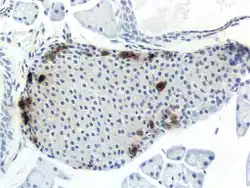

Through different microscopy techniques, the structural related details of PP cells have been able to be better understood. This is inclusive of how big they are, what their cellular membranes look like, the proteins associated with them, and even their size. PP cells are elongated cells. Another one of these details can be noted in insulins secretory granules, or container like buds, that store insulin within a cell. In PP cells, the size of the insulin granules are smaller and spherical and similar to those in alpha cells. This is noted in human PP cells, but different animals have been shown to have different sized granules compared to humans, like rodents. In cats and dogs, PP cells have large granules.[6] In rats, PP cells have few granules, similar to humans. In dogs, some PP cells are located in the walls of the antrum of the stomach.[3]